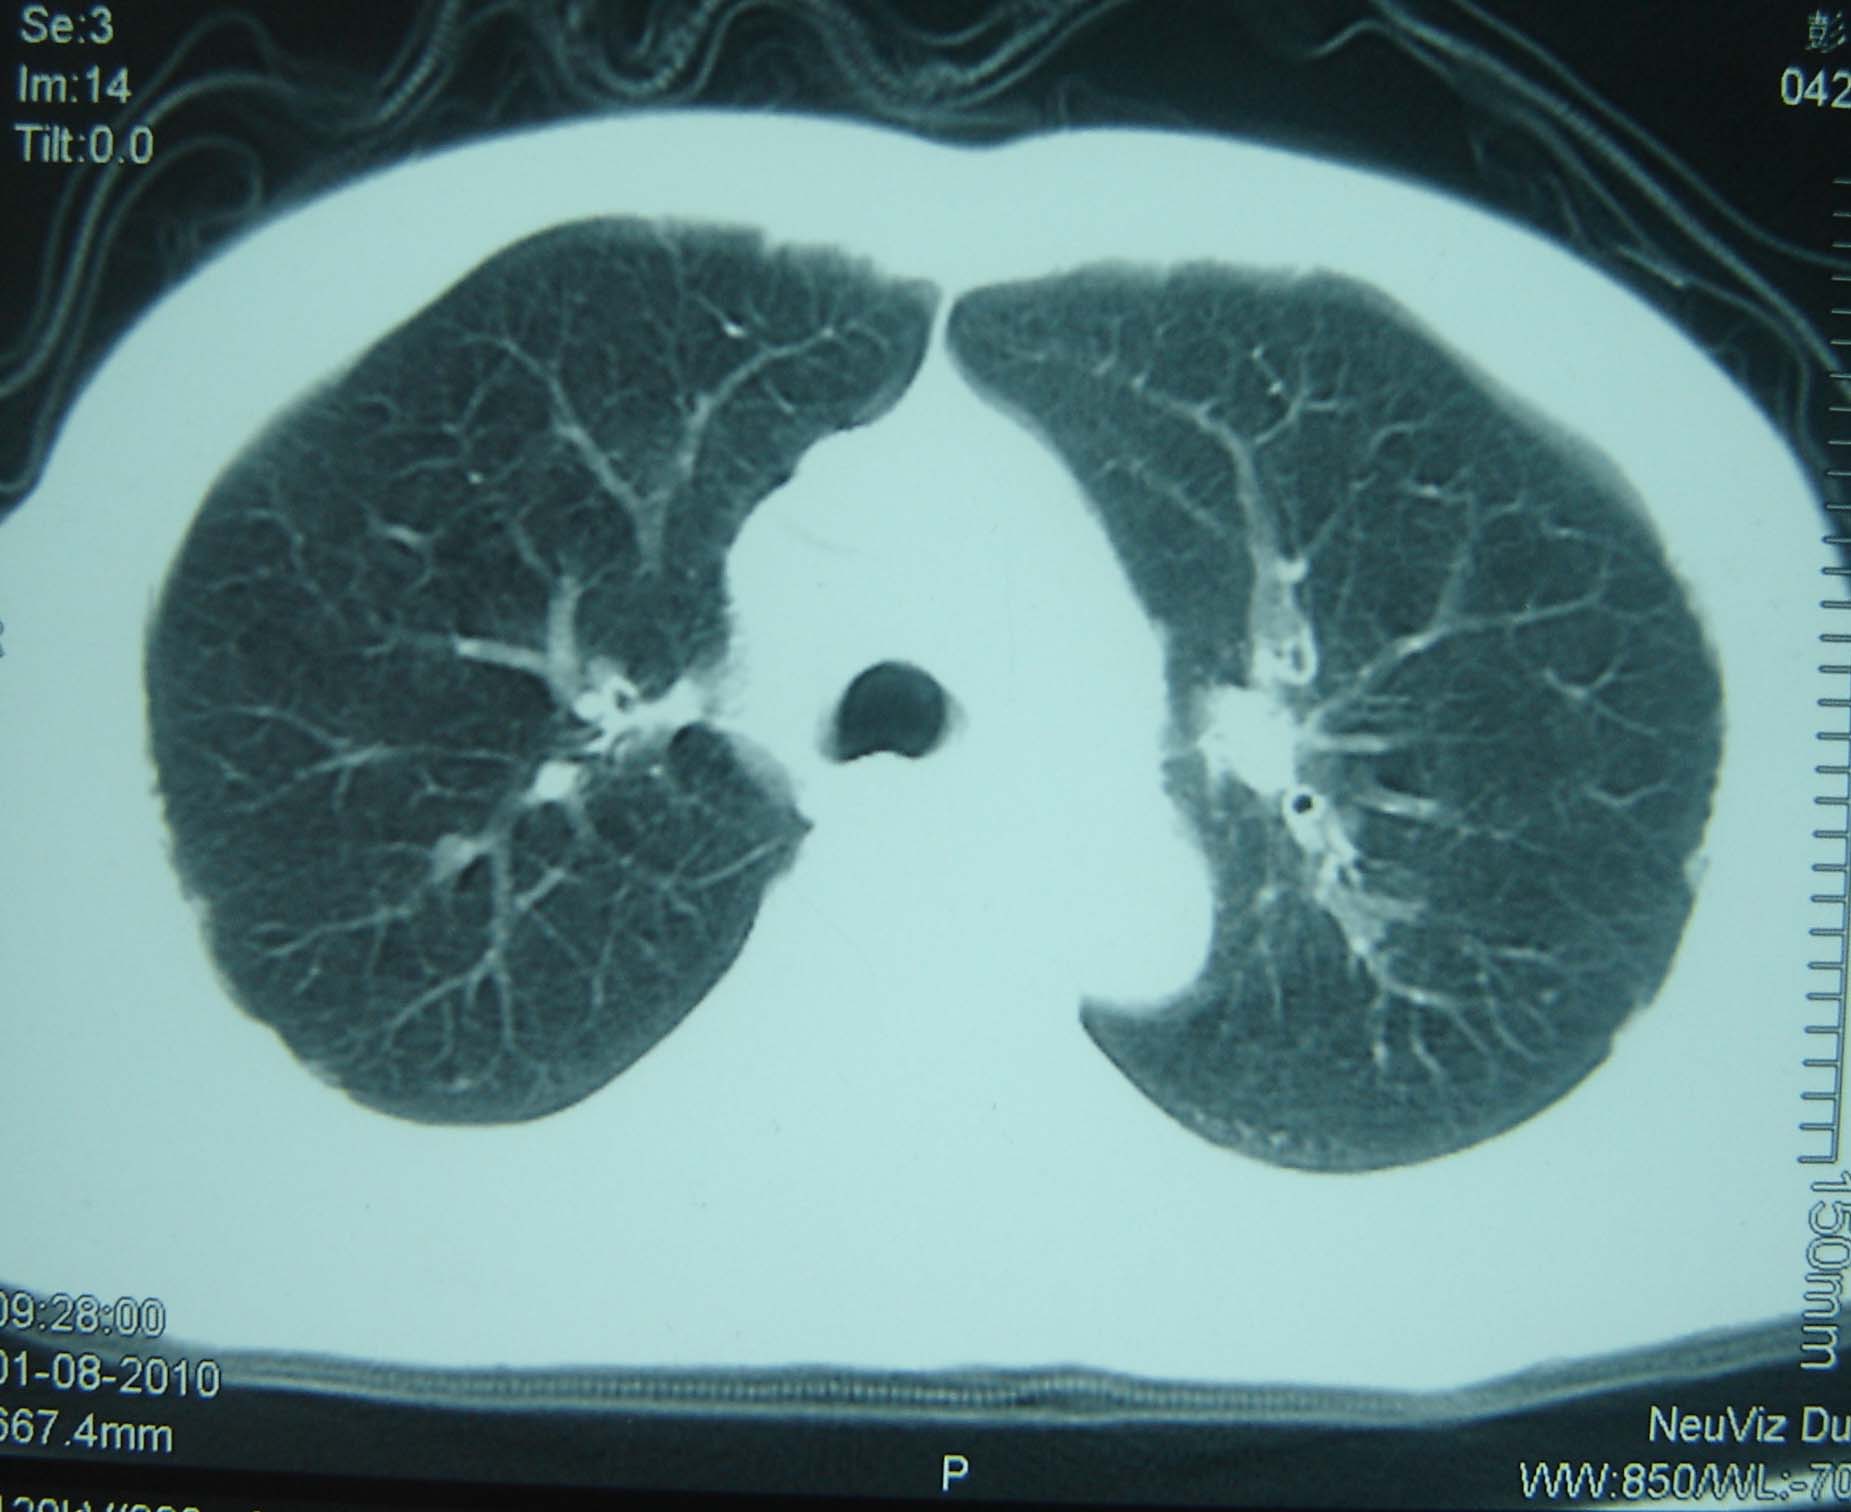

男 、43岁,咳嗽胸痛,装修工,平时接触粉尘较多,有吸烟史10多年,纤维支气管镜检查未发现异常,胃镜、腹部b超检查亦未发现异常,颈部淋巴结活检未发现肿瘤细胞。

不能排除转移,如果不能找到原发灶,只有短期随访。

结节病?转移瘤?

结节病。

转移瘤?

1)考虑双肺及胸膜多发性转移瘤。2)肺气肿。

双肺结节病。